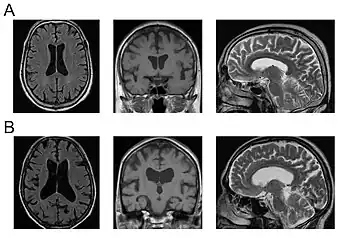

| a,b)MRI of mild and severe chronic VE showing severity-dependent enlargement of the lateral and third ventricles | |